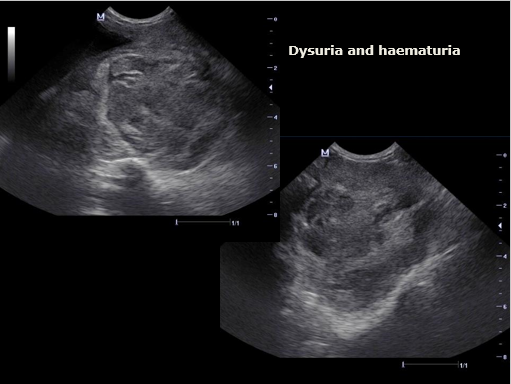

Hamatouria, dysuria

What can be seen?

2 ST opacity – maybe bladder and prostate

How does the overall echogenicity compare to the normal prostate?

What is the liekly diagnosis?

Hypoechoic

More heterogenous (marbled appearance)

Slightly enlarged

Likely Diagnosis:

Acute prostatitis ** was this

Neoplasia possible

Note: there are not enough fluid cavities for cystic disease